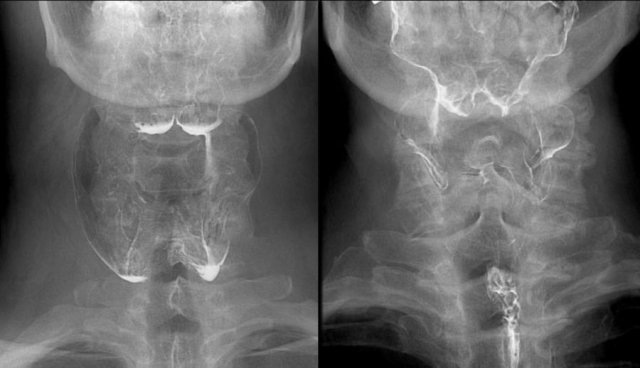

Asymmetry (2)

The case on the left is an odd case, but it nicely demonstrates the difficulty that sometimes exists in determining the cause of asymmetry.

On the far left asymmetry is seen on the fluorographic study (green arrow).

It looks as if there is something in the right pyriform sinus.

On the double contrast view on the right the pyriform sinus is normal (green arrow), but at the level of the vallecula on the right a lobulated proces is seen (yellow arrow).

At a higher level a smooth indentation of the oropharynx is seen (blue arrow).

The lobulated tumor at the level of the valleculae proved to be remnants of the lingual tonsil, which is a common finding and sometimes difficult to differentiate from cancer of the tongue base.

Continue with the CT of this patient.